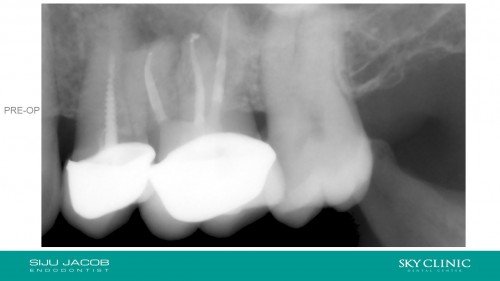

Selective Re-treatment of Distal Root

By Siju Jacob / August 20, 2018

Patient came in with a sinus tract and lesion in the distal root. I Re-treated […]

Resolved.